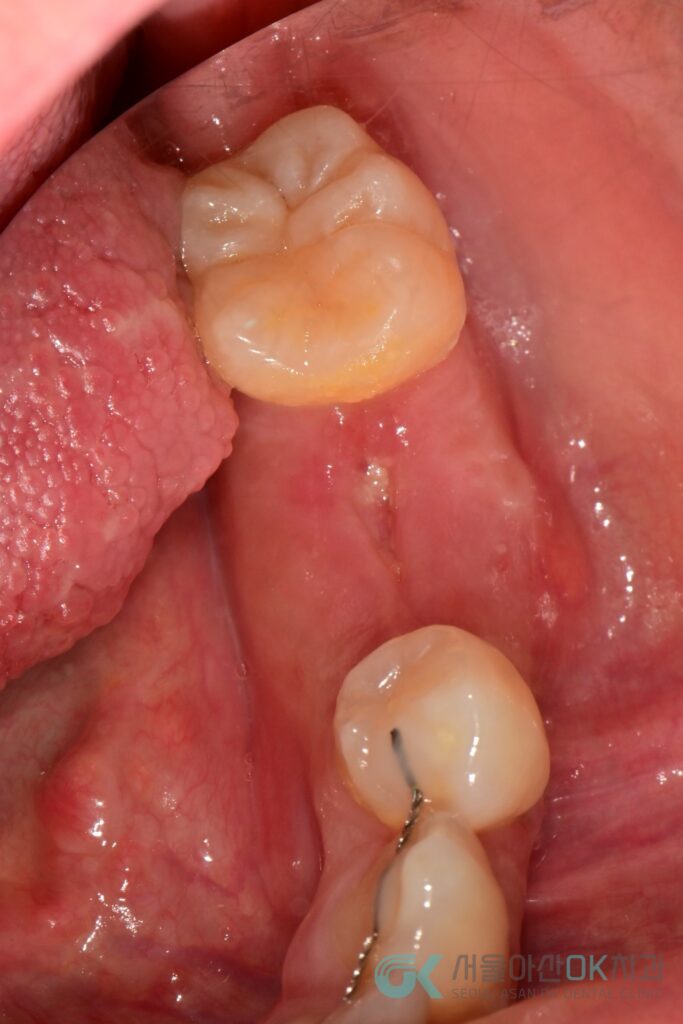

4) 4차 목표 : 임플란트 1차 수술 + 추가 GBR

2025-04-19 #36 임플란트 1차 수술을 시행했습니다.

- 시스템: OSSTEM SSIII SA

- 사이즈: Φ4.0 × 8.5

- 골질: D2

- 초기 고정: 50N 이상

- 수술 기록상: 얇은 협측 ridge(얇은 뼈) + 추가 GBR(이종골) 병행

즉, 발치 즉시 GBR로 “기본 골량”을 만들었지만,

실제 식립 시점에도 협측이 얇아 추가로 뼈를 보강해 장기 안정성을 높인 케이스입니다.